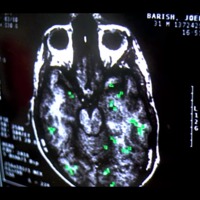

Eternal Sunshine of the Spotless Mind (Michel Gondry, 2004) illustre comment les technologies peuvent être employées pour supprimer un souvenir ou des sentiments douloureux. Le personnage de Joel Barish (Jim Carrey) découvre que Clementine (Kate Winslet), sa petite amie, s’est fait effacer tous ses souvenirs liés à leur relation amoureuse. En effet, à la suite d’une dispute survenue entre eux, Clementine a pris la décision de ne plus se souvenir de Joel et a fait appel à l’entreprise spécialisée dans l’effacement de mémoire Lacuna Inc pour y parvenir. Impuissant face à cette situation à l’égard de laquelle il n’a pas été consulté, Joel fait appel à la même entreprise afin d’effacer à son tour les souvenirs qu’il a de Clementine. Effacer un souvenir au moyen de la technologie Lacuna nécessite de suivre trois grandes étapes. Le client doit d’abord rassembler tous les objets liés à la personne qu’il souhaite oublier (photos, vêtements, cadeaux, objets, etc.) et qui sont susceptibles de la lui rappeler, puis se rendre muni de ceux-ci dans le laboratoire de Lacuna. Cette collection d’objets permet ensuite au Dr Howard Mierzwiak (Tom Wilkinson) et à son technicien (Mark Ruffalo) de constituer une carte cérébrale (mapping) du client et de cibler les éléments à effacer. Exposé aux objets les uns après les autres, certaines zones du cortex cérébral du client sont activées et traduites par une machine de cartographie cérébrale. Le soir même, un groupe de techniciens se rend directement chez le client, à l’heure du coucher, pour effacer les souvenirs ciblés. Le client se réveillera le lendemain matin, dans son lit, comme si rien n’était arrivé. L’effacement de la mémoire épisodique s’opère grâce à un casque métallique imposant relié par de multiples branchements à un ordinateur. Le technicien supprime un à un les souvenirs identifiés lors de la cartographie cérébrale. Une fois la suppression effective, Lacuna envoie un faire-part aux proches du client pour les avertir de ne plus mentionner à celui-ci le nom de la personne oubliée. L’entreprise Lacuna assure que sa technologie est efficace, mais elle mentionne tout de même que certains clients pourraient présenter des résistances à l’effacement mémoriel et ainsi lutter pour conserver certains souvenirs. C’est précisément le cas du personnage principal, Joel Barish.